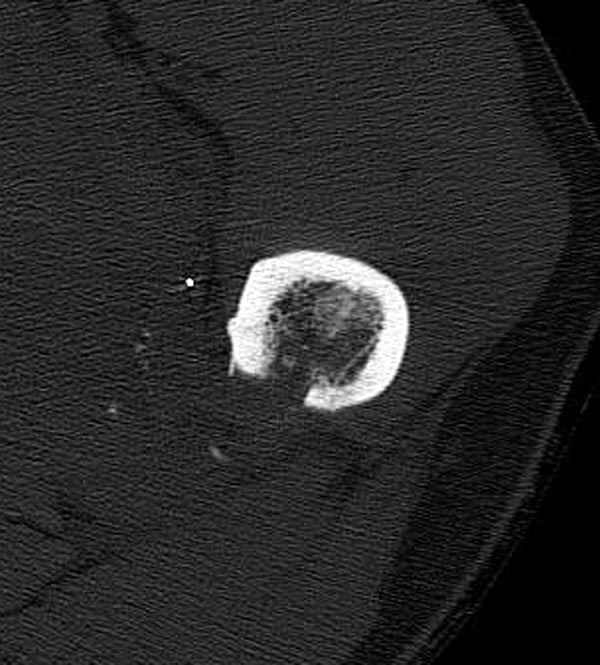

Больной с огнестрельным переломом бедра с вовлечением около 15% медиального кортекса, входное отверстие около 1 см в диаметре; стабильный, без сосудистых и неврологических признаков.

Литературные данные о влиянии кортикального дефекта на стрессовые переломы в длинных трубчатых костях в основном встречаются в онкологии, например кортикальный дефект более 50% имеет больше шанса стрессовых переломов, чем в нашем случае.

Учитывая, что больной получил травму не во время визита в церковь, и он является одним из представителем 40 миллионного “outstanding itizen”, без медицинской страховки, без работы в свои 39 лет, и без надлежающей ортопедической дисциплины у которого отсутсвует страх стрессового перелома, было рекомендовано оперативное лечение: профилактическое антеградное интрамедуллярное штифтование.

Методика штифтования при отсутствии большой зоны перелома как при онкологических профилактических штифтованиях, расверливание интрамедуллярного канала проводим с предварительным наложением дополнительного дренажного отверстия в дистальном отделе бедра (в данном случаи в канале оставили 6.5 мм канюлированный шуруп), иначе при создании давления в канале во время сверления имеется опасность эмболизации легочной артерии тромбом.